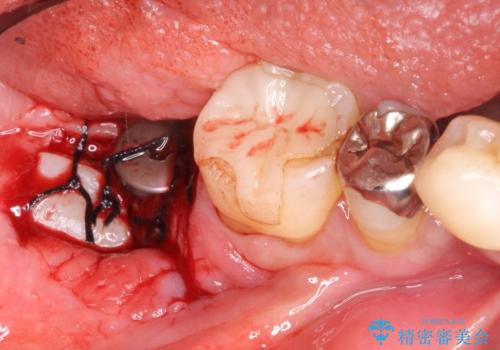

- 奥歯が痛いことを主訴に来院されました。

重度の歯周病により保存困難と診断し、抜歯後にインプラント治療を行いました。

抜歯後十分な骨の回復が認められず、単独の骨増生を行った後にインプラントを埋入しました。

インプラント埋入時に骨が足りない場合にはインプラント埋入前に骨増生を行います。また、インプラント周囲の角化歯肉が不足した場合は角化歯肉の移植も行うことがあります。